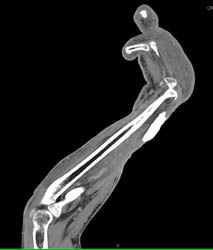

Diagnosis

Pelvic Fracture With Bleed